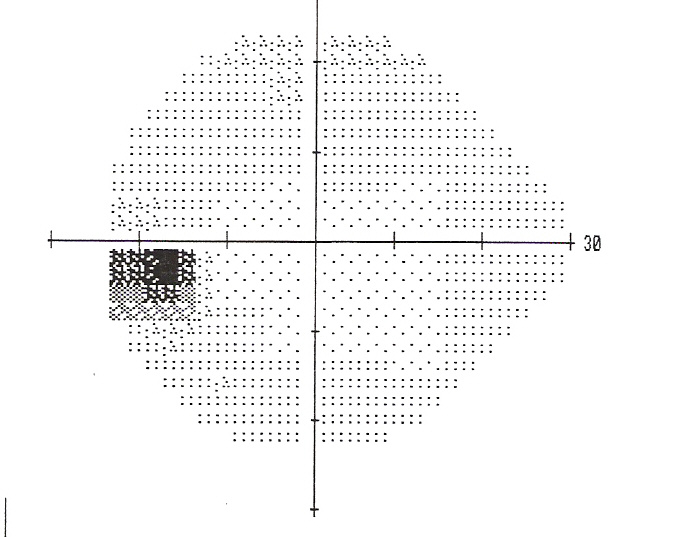

b Goldmann visual field charting showing (baring) and enlargement of Spot In Field Of Vision A scotoma is a blind spot in your field of vision. They may look to you like black or gray specks, strings, or cobwebs. Eye floaters are spots you might see in your field of vision. A scintillating scotoma is a shimmering or glittering blind spot in your vision. Flashes can look like flashing lights or lightning streaks in your. Spot In Field Of Vision.

An enlarged blind spot and peripheral visual field defects in the right Spot In Field Of Vision Blind spots may be small or large and can be temporary or permanent. “ scotoma ” means “blind spot,” and scintillating. If you try to look at them. A scotoma is a blind spot in your vision, which is an area you cannot see. A scotoma can also move around. They typically come and go, only becoming noticeable. They may. Spot In Field Of Vision.